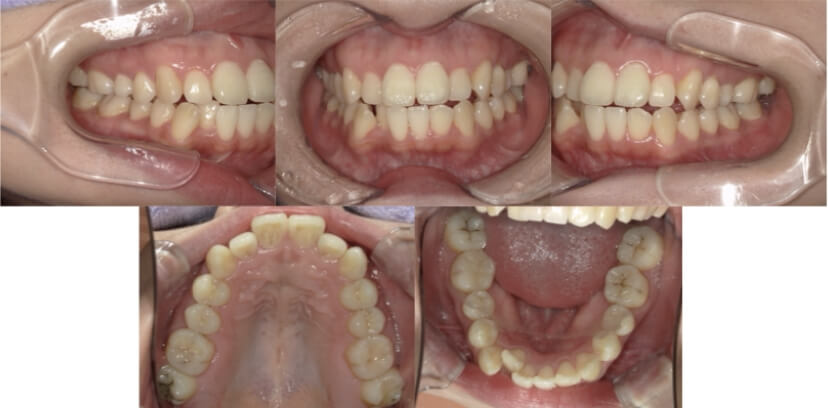

症例3

叢生

抜歯

ブラケット矯正

上下顎叢生(上下の前歯のガタガタ)のケースです。

装置はラビアル(上下表側)で、上下顎の小臼歯を4本抜歯を行っています。抜歯したスペースを使って、上下の前歯の後方移動と叢生(ガタガタ)の改善を行っています。

主訴 八重歯を治したい。

年齢・性別 25歳 女性

お住まいの地域 神奈川県川崎市

治療方針 抜歯スペースを利用して上前歯の叢生(ガタガタ)の改善

抜歯部位 上下顎左右第一小臼歯

使用装置 ラビアル(上下表側)、顎間ゴム

治療期間 1年11か月

治療回数 16回

リテーナー クリアリテーナー

BEFORE

AFTER